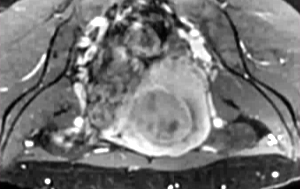

28 岁女性,下腹部疼痛及腹部紧张症状

![]() |

| 治疗前后对比 |

随访

| 6个月和12个月随访 |

44岁,患有盆腔疼痛和阴道出血症状